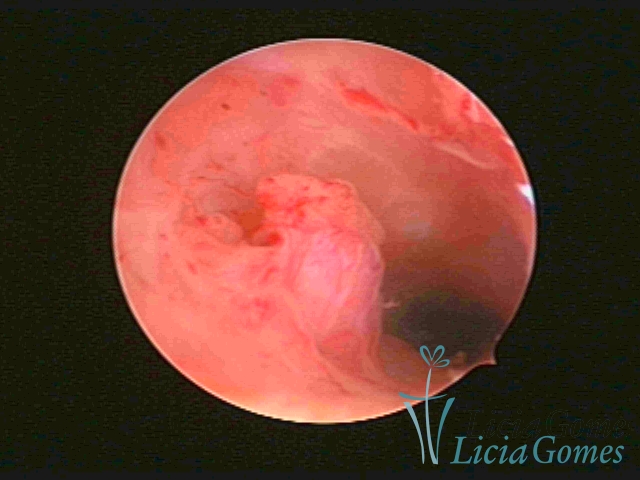

ENDOCERVICAL POLYPS

Benign tumors resulting from the reactive focal proliferation to inflammatory processes or hyperestrogenism situations, which may be sessile (with a large implantation) or stalked.